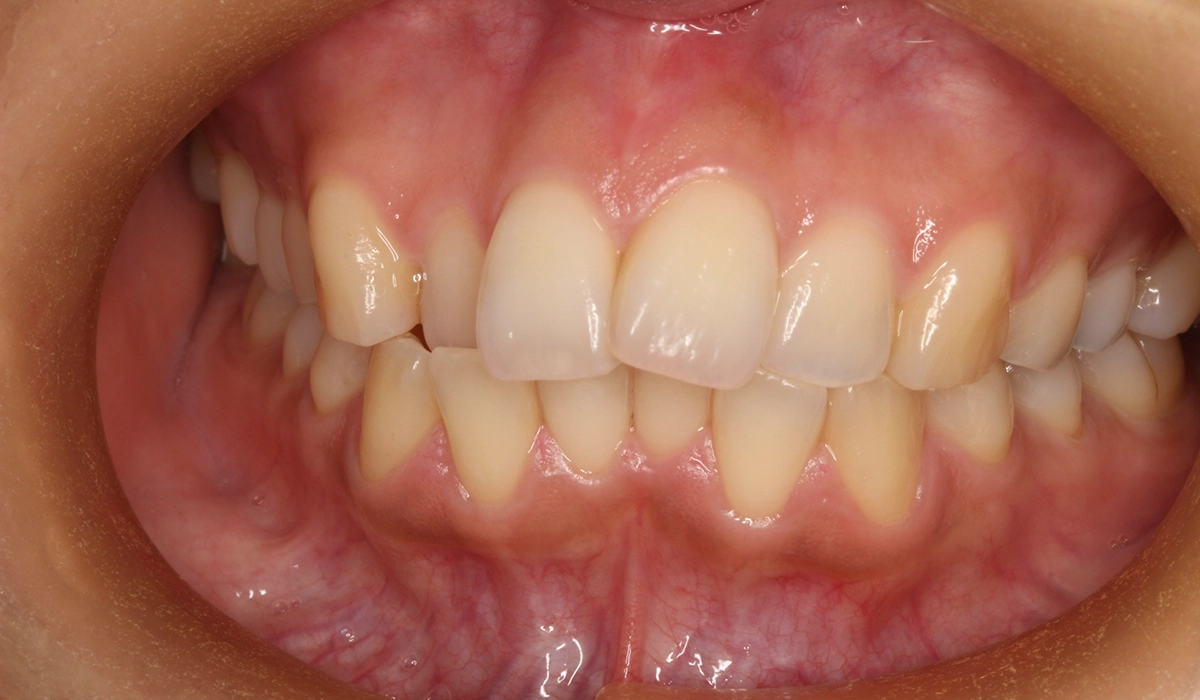

術前:正面

今回ご紹介する患者様は、上下前歯部のがたつきを気にされており、検査後Ⅰ級叢生と診断いたしました。左上7番予後不良により抜歯し、左上8番を配列したためやや治療期間が長くなるも満足いく配列となり患者様も満足していただけました。

| 主訴 | 上下前歯部のがたつきが気になる |

| 治療内容 | 上下前歯部のがたつきを気にされており、検査後Ⅰ級叢生と診断いたしました。左上7番予後不良により抜歯し、左上8番を配列したためやや治療期間が長くなるも満足いく配列となり患者様も満足していただけました。 |